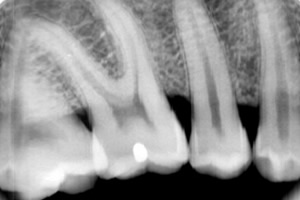

O novo equipamento utiliza o mesmo princípio dos aparelhos convencionais, mas, em vez de impressionar uma base de prata, a radiação incide sobre um filme fotoluminescente constituído por sais de terras-raras, entre outros materiais, excitando as cargas eletrônicas das moléculas das substâncias que o compõem. “Ao interagir com os raios X, as moléculas atingem um estado metaestável; em seguida, um laser é utilizado para escanear o filme, varrendo sua superfície”, explica o Prof. Dr. Vanderlei Bagnato, coordenador do CePOF.

Ao incidir em cada ponto do filme, o laser fornece energia necessária para que essas moléculas emitam uma luz azul. “Quanto mais luz, mais radiação sobre o filme, o que permite mapear toda a intensidade de raios X”, resume Bagnato.

A utilização de filmes em raios X digital já era tecnologia conhecida; a novidade está no escâner a laser que “lê” o filme e encaminha em tempo real a imagem gerada para um monitor de alta resolução. O processamento da radiografia digital exigiu também o desenvolvimento de softwares com aplicativos que permitem não apenas visualizar a radiografia, mas também observar, por exemplo, a densidade óssea. A parte óptica do laser foi desenvolvida pelo CePOF, e a plataforma eletrônica e o programa de processamento, pelo Instituto Atlântico, no Ceará.

O equipamento de raios X digital melhora a qualidade das radiografias realizadas em consultórios odontológicos e reduz a radiação em até 80%. “A baixa densidade de raios X é compensada na leitura, já que o escâner permite controlar o grau de resolução”, explica Bagnato.